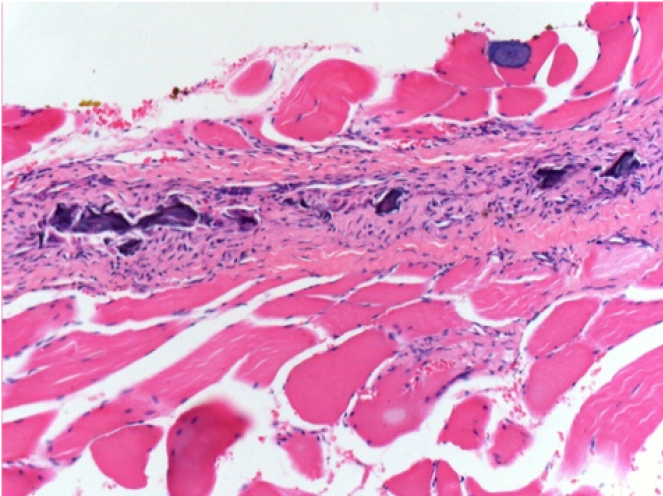

1 month after Endopeel Injection 0.1ml in the right pretibial muscle.

What is seen in black on the pictures is not a necrosis like could imagine some scientifics !

In fact, 4 conclusions have to be taken in consideration